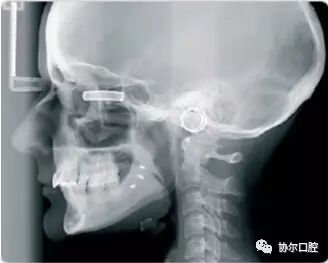

头颅定位摄影:

可进行头颅侧位和后前位摄影

CRANEX D 可进行标准成人全景摄影,小儿全景摄影,区域全景摄影,TMJ摄影,鼻副窦摄影和头颅定位摄影。将前牙扫描层厚增加50%,提高前牙区图像质量,并使病人定位简便。